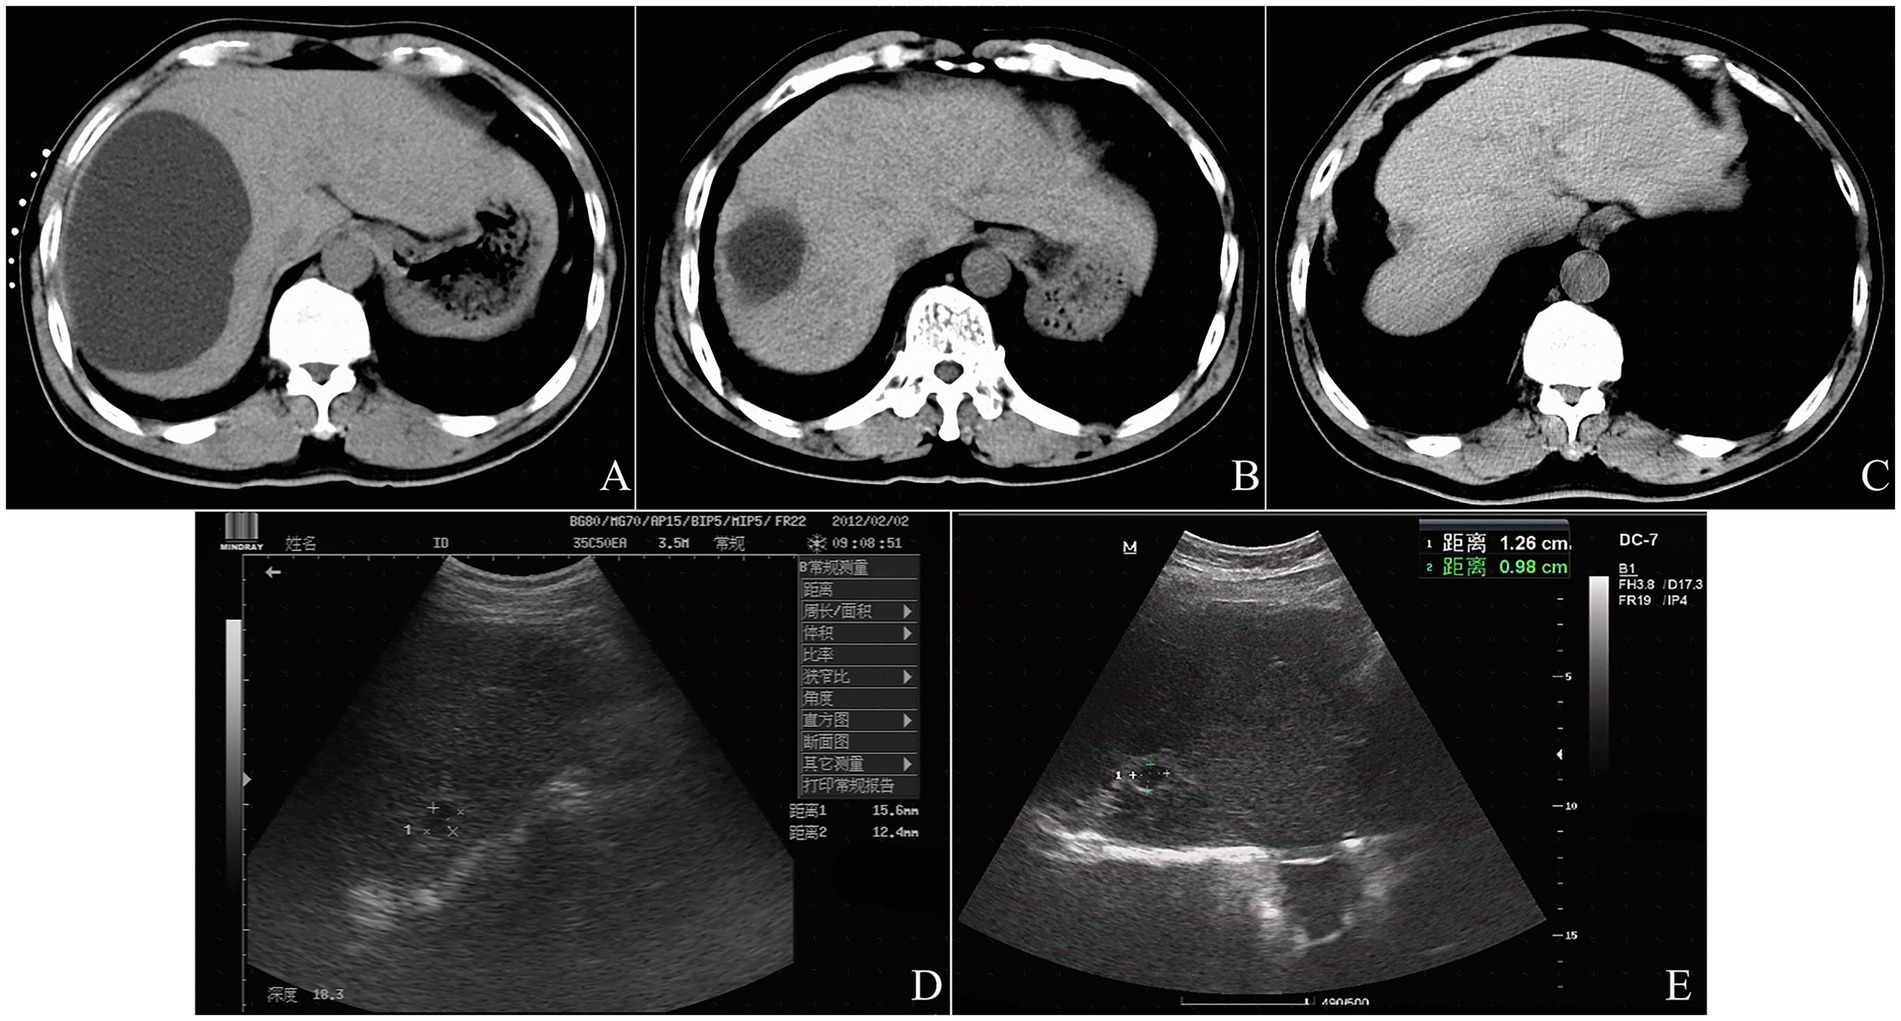

Large multiple cysts could be treated by the single-point, multi-angulated puncturing technique, which involved using the same cutaneous puncture site but adjusting the needle’s insertion angles to successively penetrate each planned cyst (Figure 2). The technological process for treating each cyst was identical to that used for the solitary cyst. The multipoint puncturing technique for multiple cysts was similar to the single-pass, single-needle puncture method, except that the former involved multiple puncture points.

Six-panel CT scan series from A to F demonstrating the single-point multi-angulated puncturing technique for multiple hepatic cysts. Needle repositioning and sclerotherapy steps are shown.

Figure 2. The single-point multi-angulated puncturing technique of CT-guided percutaneous needle aspiration and bleomycin sclerotherapy for three cysts in a 70-year-old female patient with polycystic liver disease. A 15-cm 21-gage Chiba needle was inserted toward the ventral orientation from the right midaxillary line, and went through the cyst located in the lateral section of liver segment V and entered into the cyst located in the medial section of liver segment V (A). The cyst located in the medial section of liver segment V was evacuated completely (B), and bleomycin solution contained diluted contrast media was injected into the cyst cavity without evidence of leakage (C). The needle was then withdrawn into the cyst located in the lateral section of liver segment V, the procedure of aspiration and sclerotherapy was repeated (D). Next, the needle was drawn back to the subcutaneous layer, and than was inserted toward the dorsal orientation from the right midaxillary line and entered into the cyst located in liver segment VI; the procedure of aspiration and sclerotherapy was performed (E). The postprocedure CT scan revealed that bleomycin solution remained behind in three cysts without evidence of spillage (F).